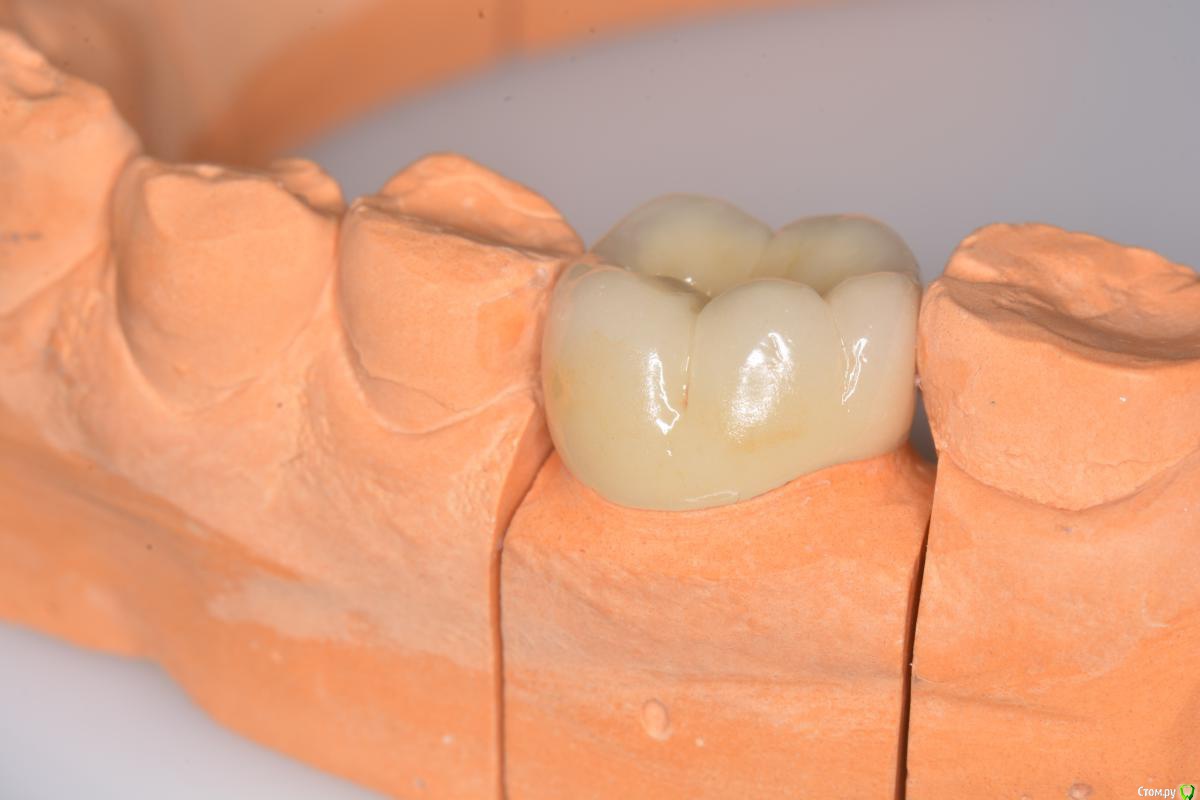

togrul Опубликовано 3 марта, 2015 Поделиться Опубликовано 3 марта, 2015 (изменено) Добрый вечер. Снимки в день сдачи. Изменено 3 марта, 2015 пользователем togrul 4 1 Ссылка на комментарий

Aquarius Опубликовано 3 марта, 2015 Поделиться Опубликовано 3 марта, 2015 Добрый вечер. Снимки в день сдачи.Отлично! А эта десневая маска мягкая? Ссылка на комментарий

togrul Опубликовано 3 марта, 2015 Автор Поделиться Опубликовано 3 марта, 2015 Спасибо. Я бы не сказал, достаточно жесткая. Жермаковская если не ошибаюсь. Ссылка на комментарий

Aquarius Опубликовано 3 марта, 2015 Поделиться Опубликовано 3 марта, 2015 Спасибо. Я бы не сказал, достаточно жесткая. Жермаковская если не ошибаюсь.Я несколько раз недосаживал работы из-за масок. После пыток техники сознавались, что чуть-чуть срезали дёсенку на профиле прорезывания((( И всё...... Ссылка на комментарий